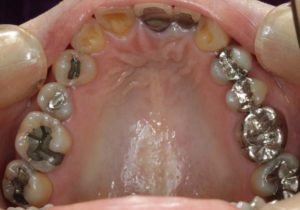

治療お疲れ様でした。たくさん銀歯が入っていたのですが、最後には真っ白になりましたね。銀歯をやり直す材料にはセラミックとプラスティックがあるのですが、基本的にできるだけプラスティックで治すようにしています。この患者さんも、可能な限りプラスティックで治し、どうしても無理なところだけセラミックにしました。そのため歯を削る量が少ないことに加え、費用もかなり抑えることができます。たくさん治しましたが、全部セラミックで治さなければならないとなっていたら、もっともっと時間も費用もかかっていたかもしれません。当院では、初診時に治療方針や期間や費用などを1時間ほどかけて詳しく説明していますので、患者さんには治療内容について十分納得していただいていると考えています。「親身になって治療してくれる」とおっしゃっていただいたことは、そういったところを評価して頂いたのではいかと思っております。

- 術前

- 術後